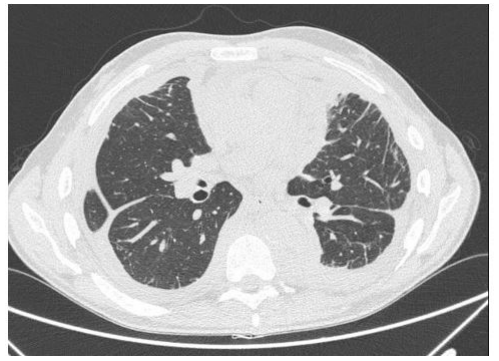

Chest X-ray showed interstitial thickening of lung, ilo-perilary congestion and bilateral pleural effusion major on the left. The findings were investigated with contrast enhanced CT of chest and abdomen, which documented the presence of solid tissue infiltrating both pleurae, mediastinal fatty tissue and pericardium, perirenal fascia and perihepatic area, and surrounding the aortic arch, the proximal tract of the epiaortic vessels.

The clinical presentation is variable as it may range from an indolent focal disease to a life threatening organ failure. [4] ECD may virtually affect any organ system. Ihe most frequently involved site is the skeleton (96% Of ECD patients), Often associated With bone pain. A pathognomonic finding is bilateral cortical sclerosis involving the diametaphyseal regions, typically observed on radiographs, associated with an abnormally strong labeling on 990iTc bone scintigraphy. Cardiovascular involvement IS frequent too (75% of cases), mostly presenting as pericardial infiltration, periaortic sheathing ("coated aorta") and myocardial infiltration [51, Central nervous system involvement appears in 51 % of ECD cases, with central diabetes insipidus being the most common finding Pulmonary involvement (43% Of cases) can lead to an interstitial lung disease or pleural effusion. ECD associated involvement of the retroperitoneal space is reported in 68% of the patients, most of which asymptomatic, and infiltration of the perirenal fat produces a typical "hairy kidneys" appearance on CT scan images [7].